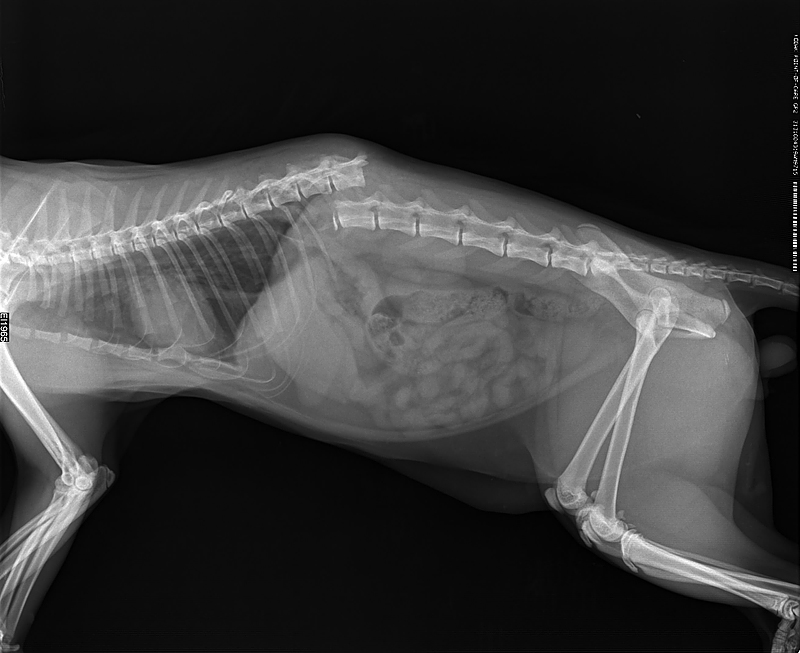

Рентгеновские снимки перелома лапы у кота: диагностика и лечение